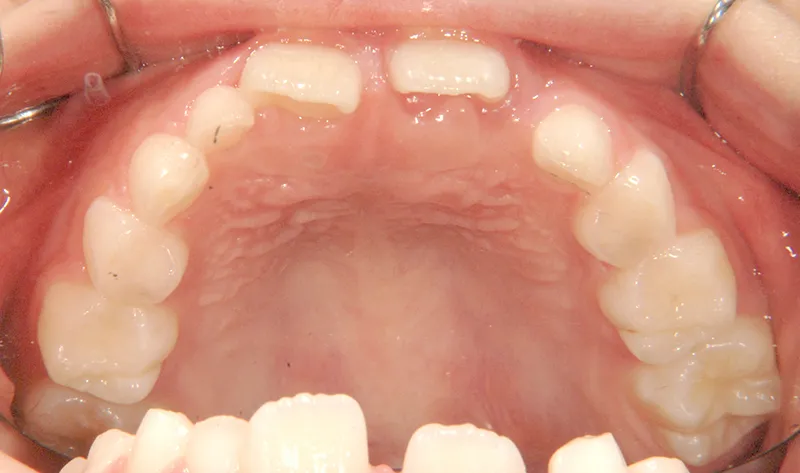

上の前歯が下の前歯より後ろに入って、受け口になっています。

下の歯は永久歯の生えるスペースがないので、オリジナル矯正装置で受け口を治して、永久歯の生えるスペースを作りました。

状態 永久歯が生える隙間がない(叢生)

受け口(下顎前突/反対咬合)